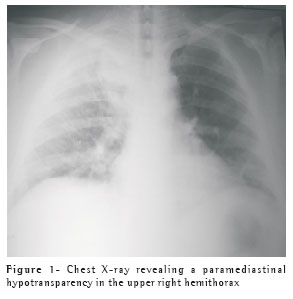

The chest X-ray upon admission revealed a hypotransparency in the upper third of the right hemithorax (Figure 1). The computed tomography of the chest revealed an image suggestive of loculated pleural empyema located in the paravertebral region of the upper right hemithorax (Figure 2). The patient was submitted to an emergency exploratory posterolateral thoracotomy, with drainage of the empyema and pulmonary decortication. He remained on mechanical ventilation for six days and was discharged from the intensive care unit on postoperative day 10, with satisfactory evolution and resolution of the infection. After the ventilatory weaning procedure and extubation of the patient, while he was conscious, we observed blepharoptosis of the right eye. The patient perceived this ptosis on the fifth day after the onset of the clinical profile and before hospitalization, a fact that was confirmed by his family (Figure 3). The patient was discharged on postoperative day 14 and presented good general health status. After two months of postoperative outpatient follow-up evaluation, the patient presented total regression of the blepharoptosis.